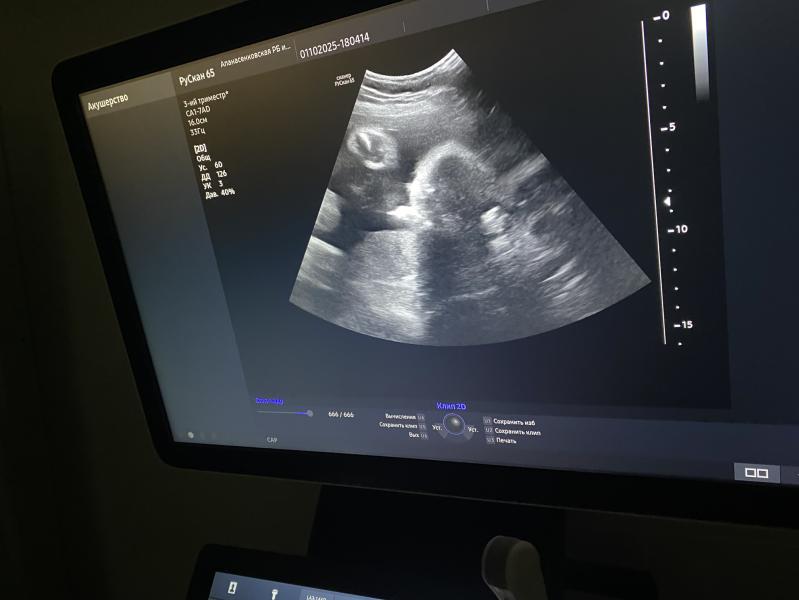

Сходила я на узи на 32 недели , сказали всё хорошо , вес 1,700 соответствует , в тазовом прилежании все хорошо , но есть одно но , обвитие вокруг шеи 😢 теперь сижу каждый раз прислушиваясь к каждому движению , даже если сильно пинает думаю что ему там плохо , у кого так же было на моём сроке ?

У меня в 33,6 тоже обнаружили обвитие

В 36 пришла на узи, уже не было